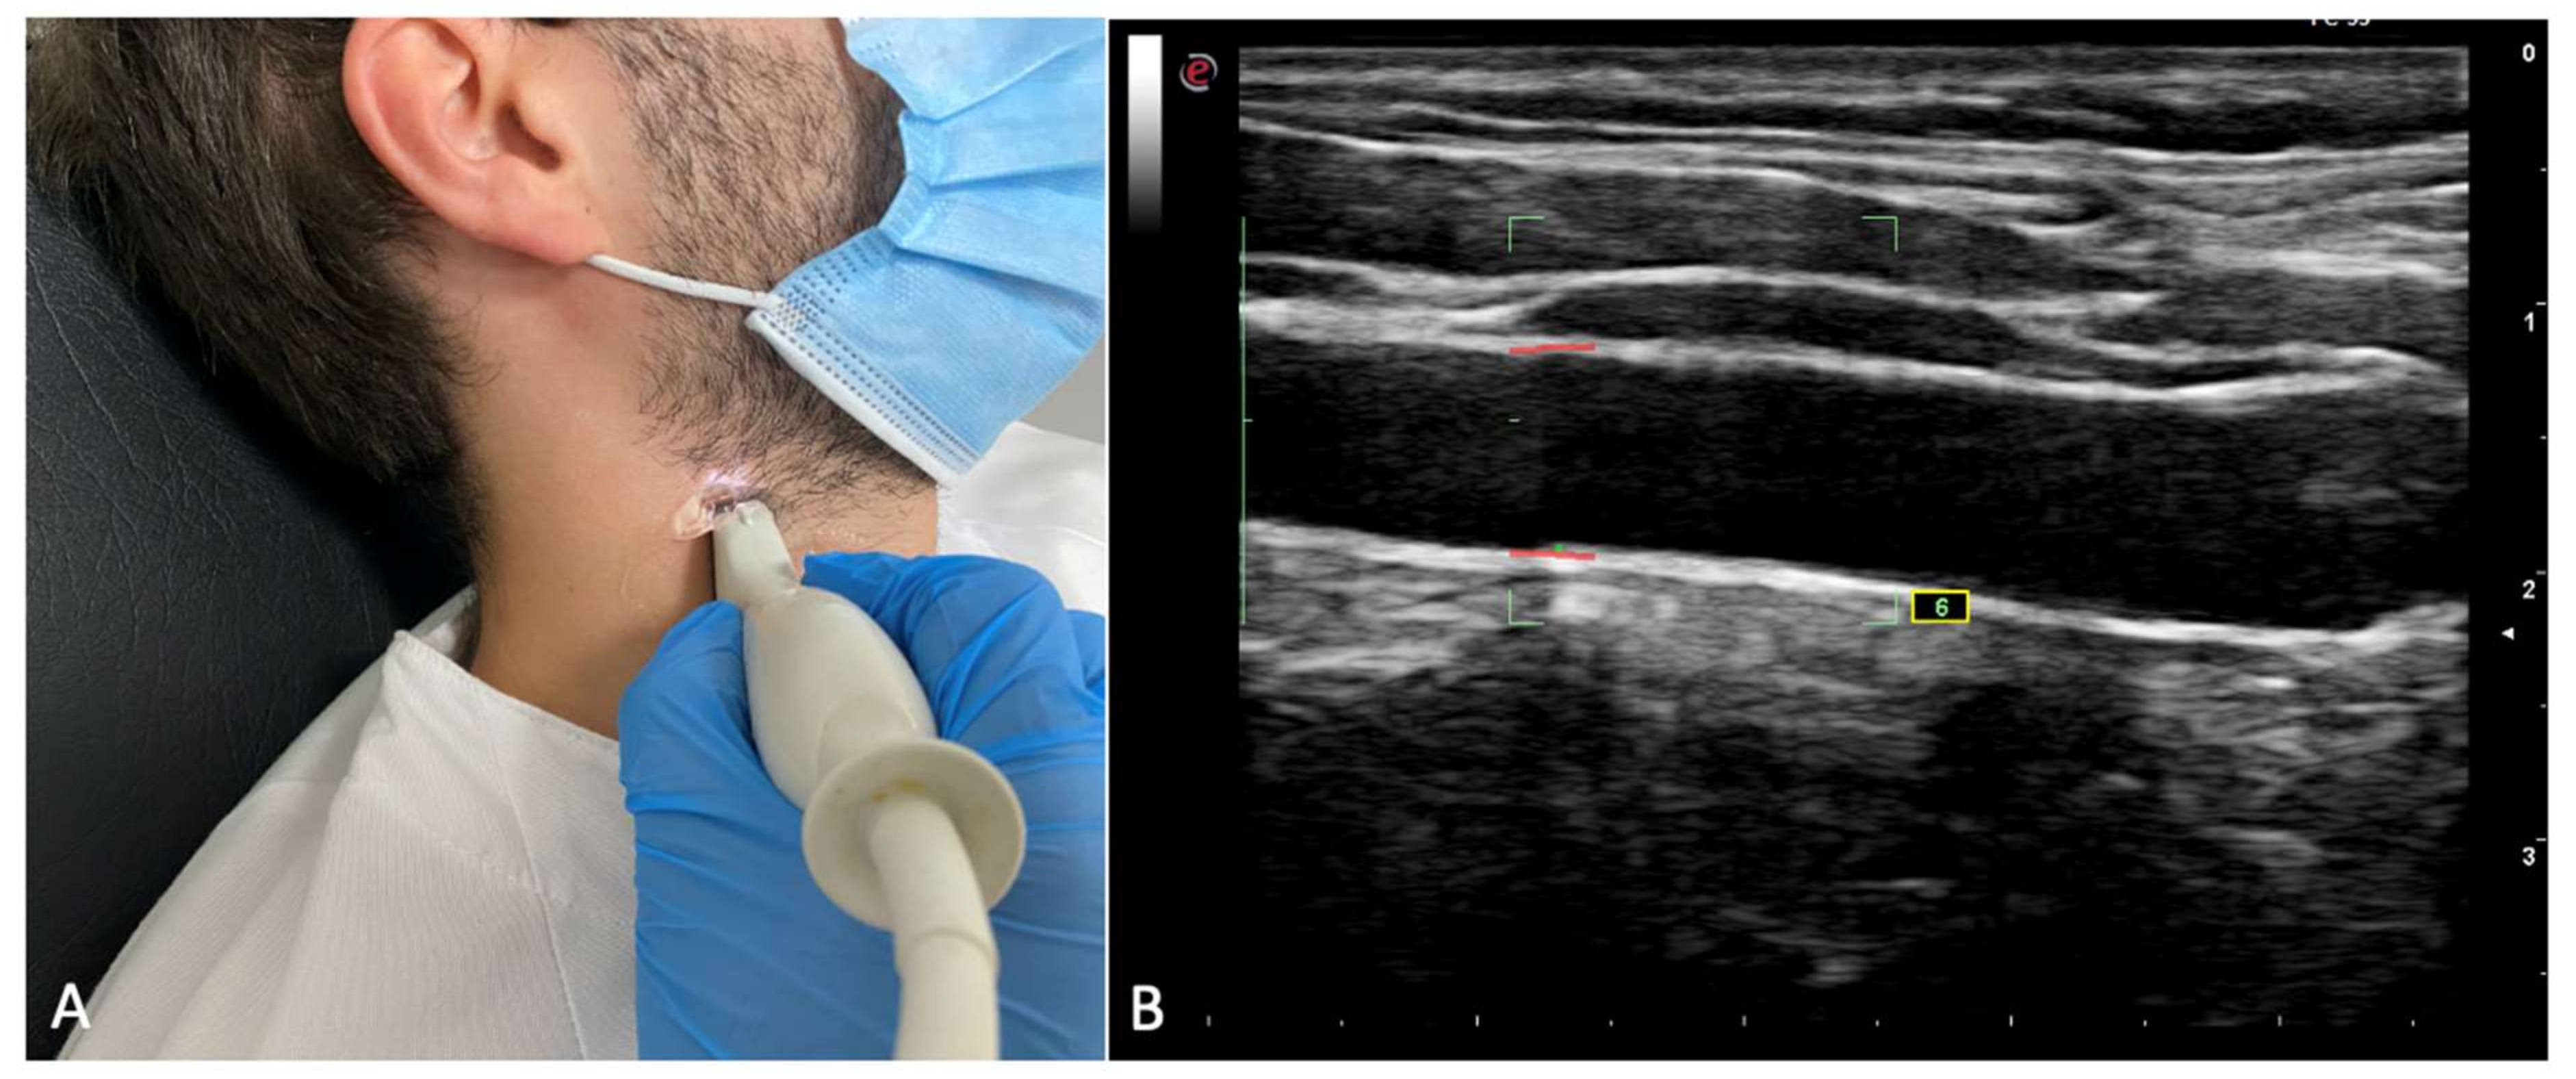

- Carotid intima-media thickness (IMT): IMT was assessed in both carotid arteries of the patients by using ultrasonography. Left, right, and mean IMT was recorded. The procedure was performed as previously described in similar investigations [25]: A complete examination of the left and right common carotid arteries was performed. Patients were in supine position with their necks being 60° laterally inclined. Six IMT measurements were performed, and in all of them, the probe was 10 mm away from the carotid bifurcation. Only those measurements with a standard deviation inferior to 20 μm were taken as valid measures. A high-resolution ultrasound scanner (Esaote MyLab Gold 25) with a 12 mHz sounding line running specific software for measuring ITM (Esaote QIMT Software) was employed. The definitive value of the IMT measurements was obtained by calculating the average of 6 valid measurements taken from the sonographic scanning. Figure 1 shows the IMT assessment.